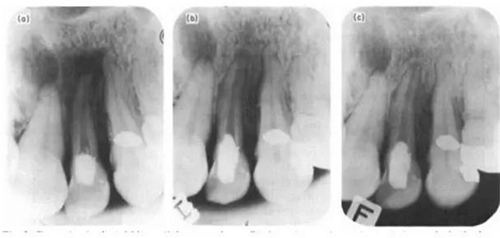

(a)-實驗開始時22根尖片,見根尖周大面積暗影;(b)-1年復診,22根尖暗影明顯縮??;(c)-2年復診,22牙周膜間隙恢復。

在Torneck之后,還有多個反駁空管理論的研究(Davis et al. 1971; Makkes et al. 1977),其中以Klevant & Eggink(1983)的實驗最為著名。他們對患有根尖周炎的實驗牙在進行根管預備后直接封閉冠部,然后進行2年的隨訪,發(fā)現(xiàn)絕大部分的根尖暗影都出現(xiàn)了愈合,只是其速率慢于充填的根管。這個重要的結(jié)果不僅駁斥了空管理論,還對以往追求根管緊密封閉的觀念提出了挑戰(zhàn)。